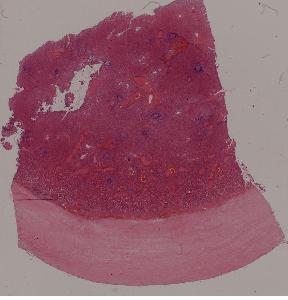

1.心肌褐色萎缩心肌肥大

2.肾曲管上皮混浊肿胀

3.肝细胞脂肪变性

4.脾包膜玻璃样变

5.血管壁纤维样坏死

6.肝细胞凝固性坏死

7.脑液化性坏死

10.肝淤血

11.淤血性肝纤维化

12.急性肺淤血

13.慢性肺淤血

14.混合血栓

15.机化血栓

16.肾贫血性梗死

17.肺出血性梗死

18.假膜性肠炎

19.蜂窝织性阑尾炎

20.肺脓肿

21.慢性扁桃体炎

22.慢性宫颈炎

第一页